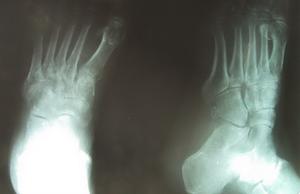

脊髓空洞症伴發上肢關節破壞者約占25%,除關節病變外尚有單側或雙側溫度覺喪失,因此上肢皮膚可見燙傷疤痕。脊髓梅毒,也叫脊髓癆,常累及膝、髖、踝和腰椎。骨、關節改變之外,可見運動性共濟失調、下肢深感覺障礙Arggll-Robertson瞳孔、血清康瓦氏反應陽性。脊髓膨出,踝和足小關節受累多見。足底有無痛性潰瘍,腰骶部見軟組織腫塊、皮膚凹陷或多毛、下肢肌萎縮感覺消失以及擴約肌功能障礙。糖尿病性神經病,可發生足小關節(跗跖、跖趾、趾間等)無痛性腫脹等。

雖然大多數關節都可受累,但膝關節受累約相當於所有其他關節發病的總和。受累關節的分布情況主要決定於原發病。運動性共濟失調時累及膝關節,髖關節,糖尿病時累及足部關節;脊髓空洞症最常累及上肢關節,尤其是肘關節和肩關節。常常為單關節受累,(除足部小關節外)很少超過二個或三個關節,並呈不對稱分布。

X線所見為伴有滑膜滲出的關節膨大和關節面不全脫位。通常能見到骨端硬化,但在晚期破壞性病變中也可能看不到。骨骼畸形,並在鄰近皮質的地方有明顯的新骨形成。這種新骨形成開始發生在關節囊內,然後常常向上擴展到長骨骨幹。軟組織偶可出現骨化和鈣化現象,然而這種現象可能是暫時的,甚至軟組織廣泛鈣化在隨後拍攝的X線照片上也可能消失。關節邊緣可見到形狀不規則的巨大骨贅,脫落後形成大量關節內游離體,此為本病特徵性改變。脊柱受累的X線表現(即特徵性的“鸚鵡嘴”樣骨贅),就是在缺乏局部臨床症候的情況下也十分常見。

X線檢查,早期見軟組織腫脹,骨端緻密,晚期關節顯示不同程度的破壞,間隙狹窄,骨端緻密,病理骨折,關節內游離體,骨質吸收,退變骨贅和新骨形成,以及關節脫位與畸形。